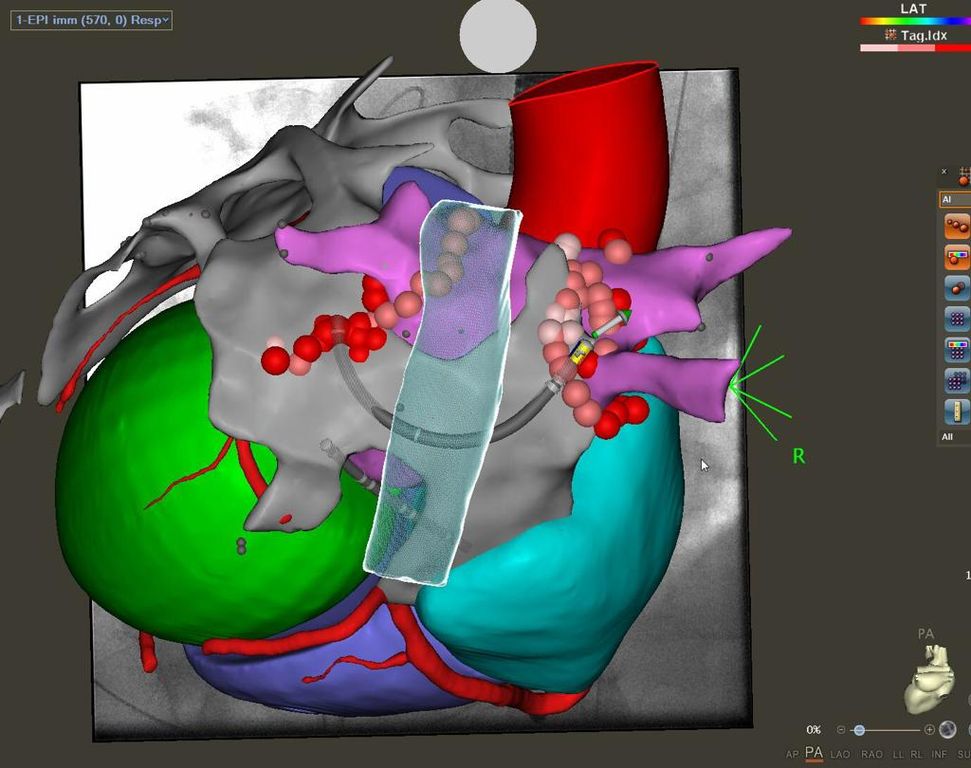

Lotta alla fibrillazione atriale: al Mauriziano un intervento unico al mondo salva la vita a un 56enne

L'operazione, eseguita dal dottor Stefano Grossi, rappresenta una novità assoluta per il trattamento della patologia e che punta ad abbattere il rischio ictus

Per la prima volta al mondo, al Mauriziano intervento rivoluzionario salva la vita ad un paziente 56enne